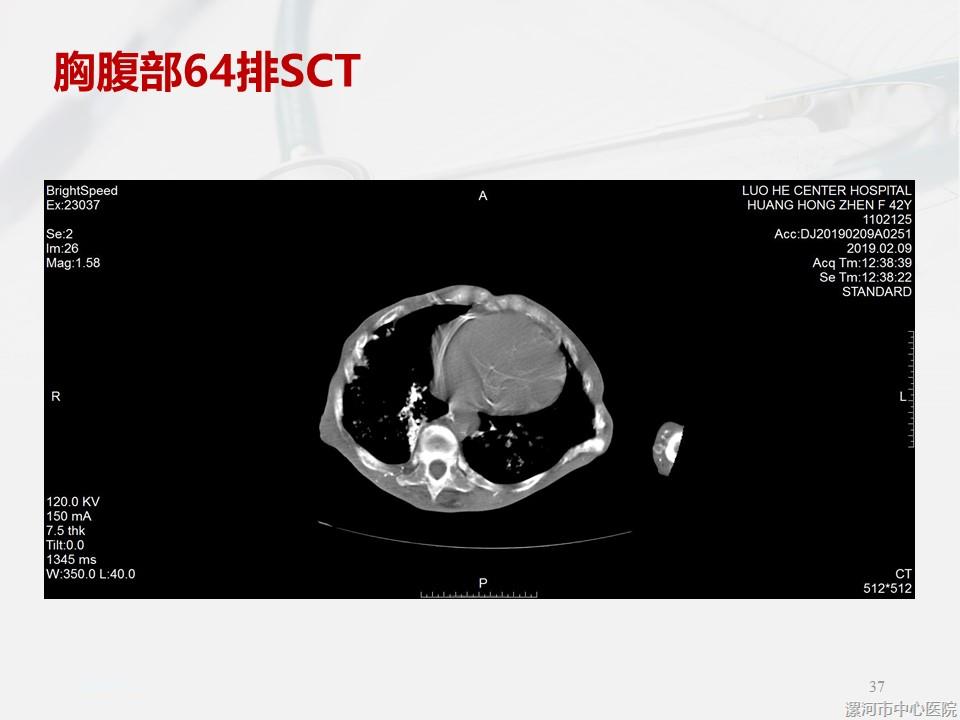

一例严重SHPT患者引发的思考